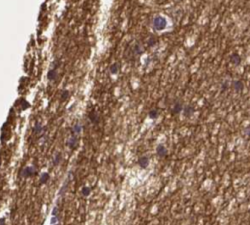

The expression profiles in both bulk and single cell RNAseq show elevated expression in brain and more specifically in inhibitory neurons, excitatory neurons, bipolar cells and astrocytes. Expression clustering and correlation of tissue and single cell RNAseq data further show SMIM17 to cluster together with other genes known to be related to Neuronal - Synaptic function and Neurons - Neuronal signaling. These findings have been partly confirmed on the protein level using immunohistochemistry that show staining of the protein almost exclusively in neuropil in cerebral cortex . This could be a starting point to further understand the function of this interesting protein.